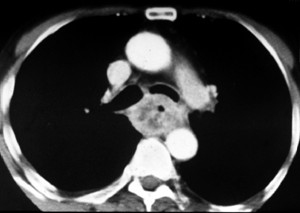

Au stade

d'extention ganglionaire ,le role du CT scanner et

echo cervicale est important pour evalue et verifie la

prognostic N0 : pas de adenopathie et N1 : adenopathie

regionale

Carcinome epidermoide de oesophage avec extention

ganglionaire N0 pas de ADP . Image TDM coupe axiale |

Tumeur de oesophage avec extention

a distance N1 au region coeliaque ( ADP coeliaque )

. Image radiologique TDM en coupe axiale |